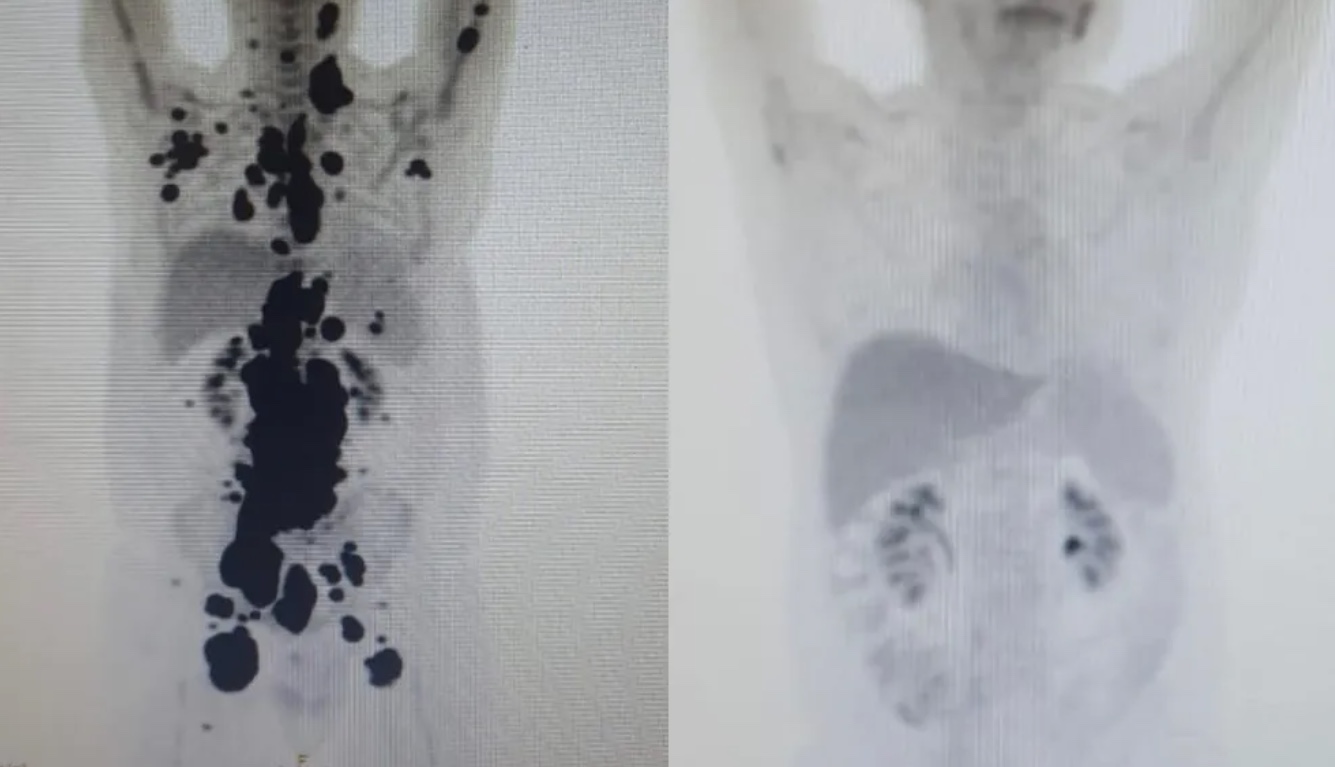

Entre eles, Paulo Peregrino, de 61 anos, que estava há 13 anos lutando contra o câncer, teve remissão completa um mês após ser submetido ao tratamento. O paciente estava prestes a receber cuidados paliativos quando foi selecionado para o teste.